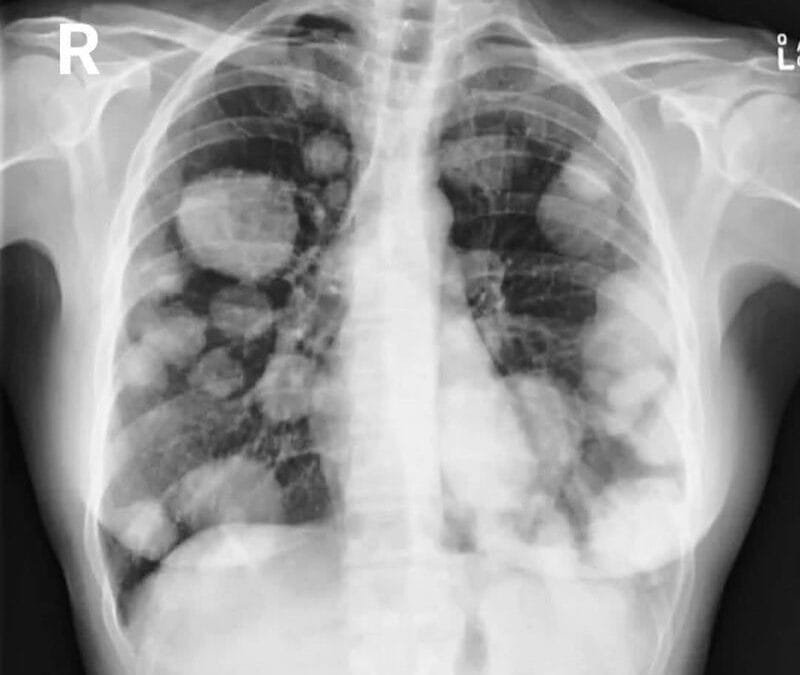

VAPEAR, UN RIESGO BANALIZADO

Desde hace años, el vicio de fumar a evolucionado hacia su versión electrónica, blanqueando el vicio, como algo menos perjudicial. Nada mas allá de la realidad, nos hacemos eco de la publicación de Eduardo García. Técnico Superior en imagen para diagnostico, con 15...